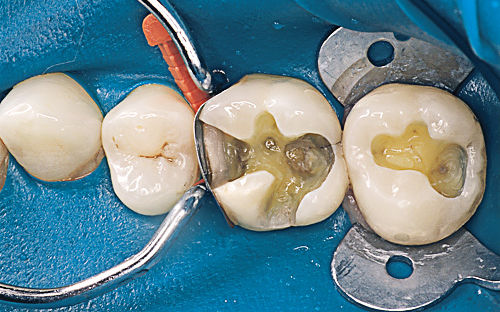

- Fillings: Restoring Your Smile

Dental fillings are one of the most common Dental Services in general dentistry. They are used to repair cavities caused by tooth decay. When a dentist identifies a cavity during a routine examination, they will remove the decayed portion of the tooth and fill it with a suitable material. Common filling materials include:

- Composite Resins: Tooth-colored and ideal for a natural look.

- Amalgam: Durable and cost-effective, often used for back teeth.

- Ceramics: Aesthetic and resistant to staining.

Fillings restore the tooth’s structure and function, preventing further decay and discomfort.